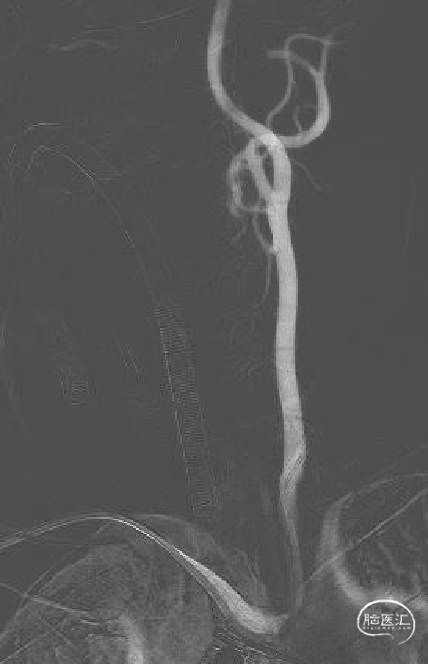

无名动脉角度较大。

左侧颈内动脉造影:大脑前动脉A2段瘤样扩张,夹层可能;颈总动脉起始部扭曲。

经右侧桡动脉通路,赛诺神畅 6F-105 APEX TRA®经桡远端通路导引导管内衬SIM2导管、泥鳅导丝,左侧颈内动脉顺利直接到位海绵窦段行3D造影。

动脉瘤无明显变化;A1开口角度较大,输送支架需注意导管是否失位。

支架头端锚定后造影定位。

术后影像。